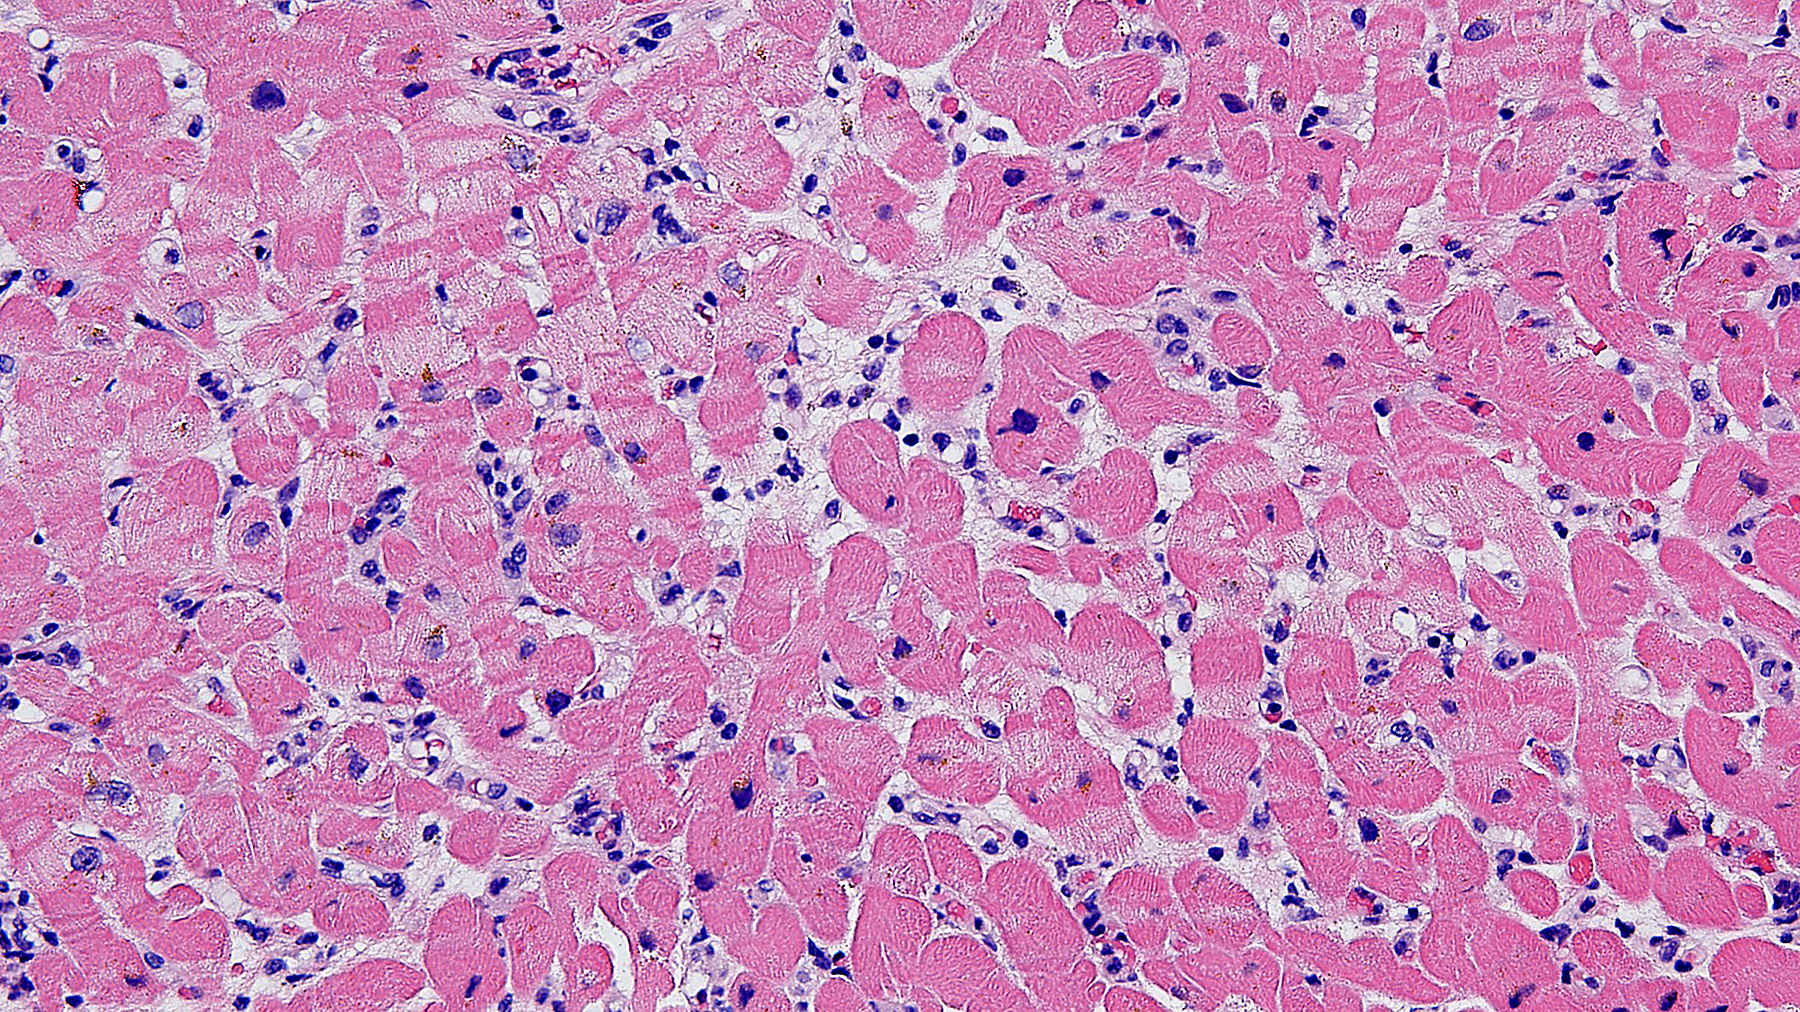

Figure B. Allograft myocardium pAMR 1. H&E (20x)